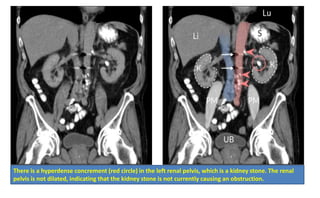

Diagnosis: Imaging

• Best initial Test : noncontrast spiral CT scan

There is a hyperdense concrement (red circle) in the left renal pelvis, which is a kidney stone. The renal

pelvis is not dilated, indicating that the kidney stone is not currently causing an obstruction.